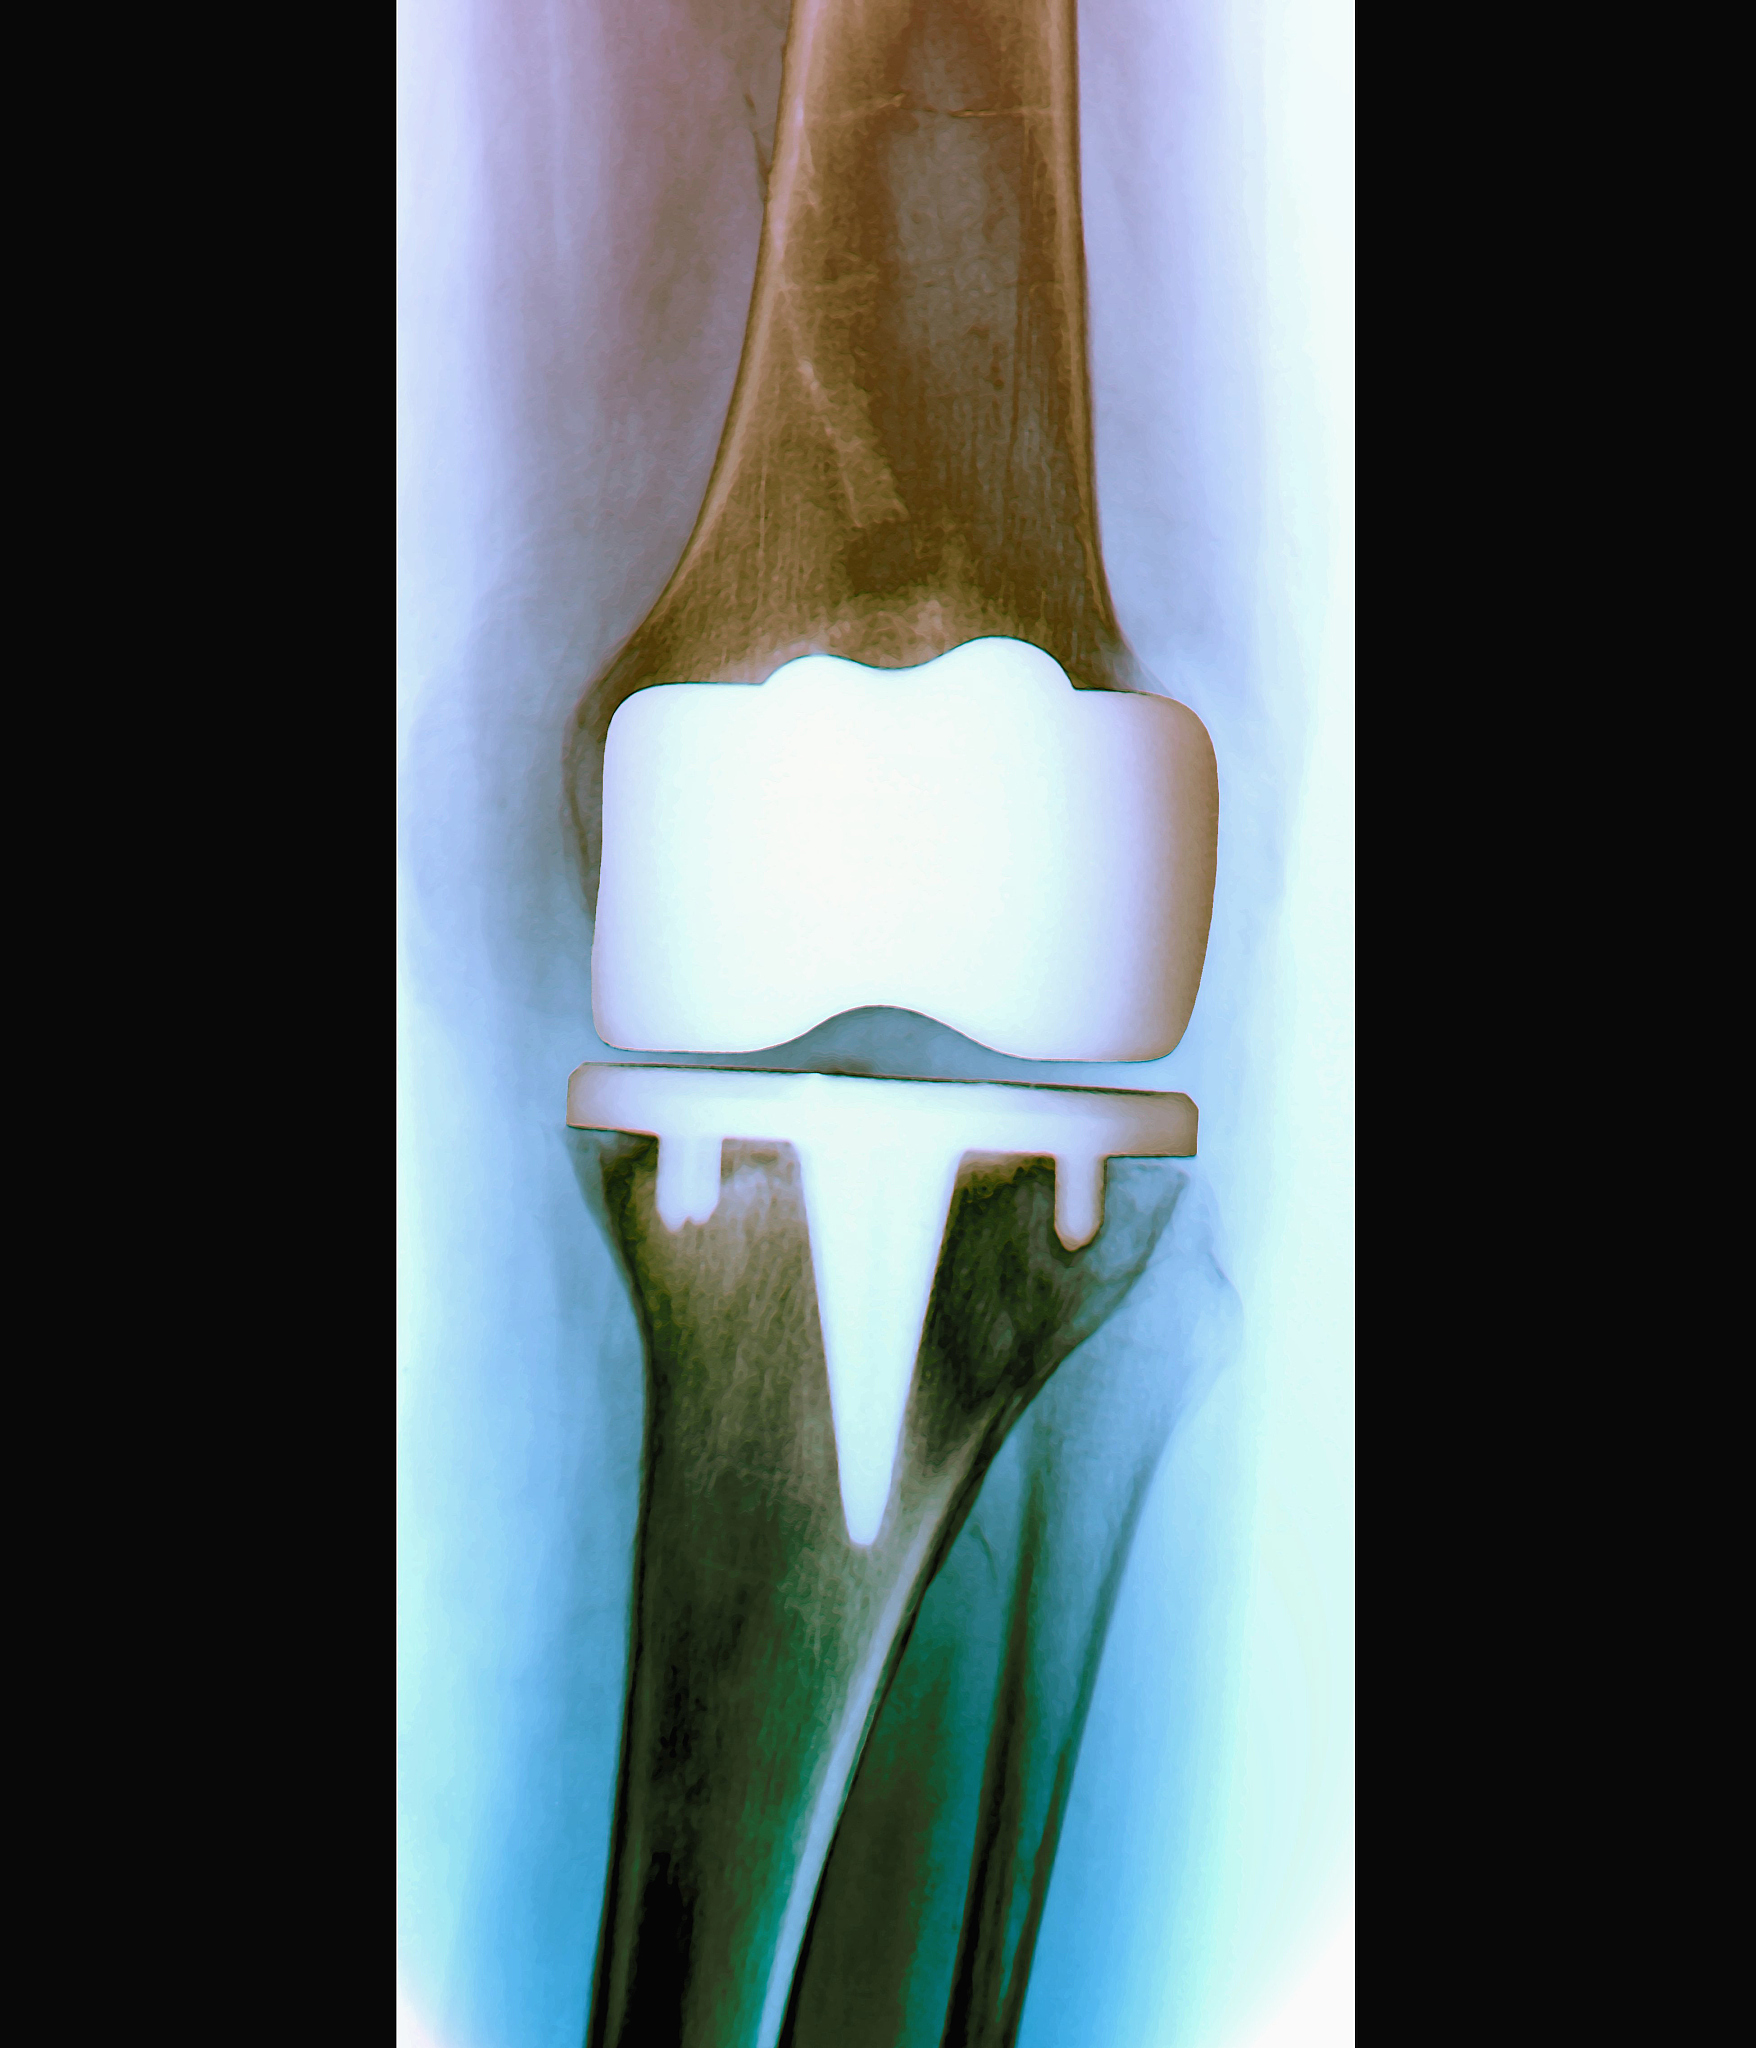

膝关节表面置换术(Knee Surface Replacement,简称KSR)是一种手术治疗膝关节骨性关节炎的方法。与全膝关节置换术相比,KSR仅替换膝关节的受损部分,保留了健康的骨骼和软组织。

1. 保留骨骼和软组织:相比全膝关节置换术,膝关节表面置换术只替换受损的关节表面,保留了健康的骨骼和软组织。这有助于减少手术创伤和术后康复时间。